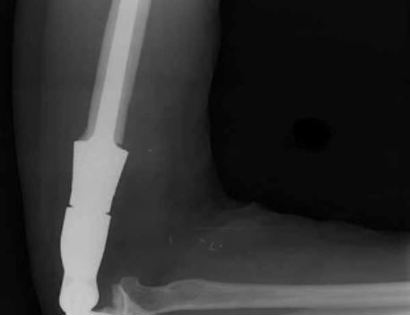

X-ray Photo

This is an X-ray image of the arm with the prosthesis.